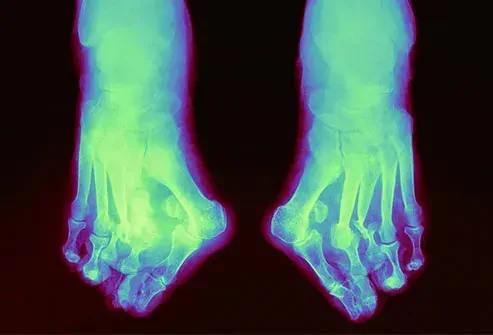

Тежката невропатия може да отслаби костите в крака ви. Те биха могли да се напукат или да се счупят, карайки крак червен възпален или топъл на пипане. Но тъй като не можете да го почувствате, може да продължите да вървите по крака и да го деформирате. Например арката може да се срине и да изпъква към земята. Хванат рано, вашият лекар може да лекува крак на Шарко със брекети за почивка и специални обувки. Сериозни случаи може да се нуждаят от операция.